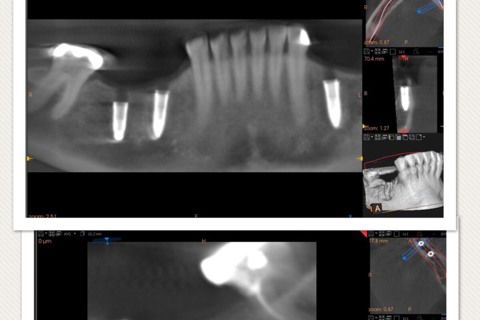

Planejamento virtual e tomografia final

tomografia final comprovando quês técnica é segura e precisa